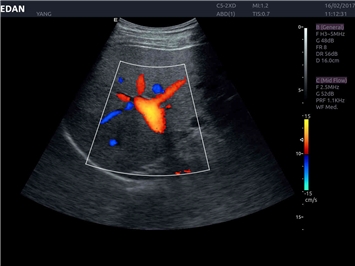

• Кардиологических исследований

Трехмерная реконструкция ЦДК:

Да

Кардиология: